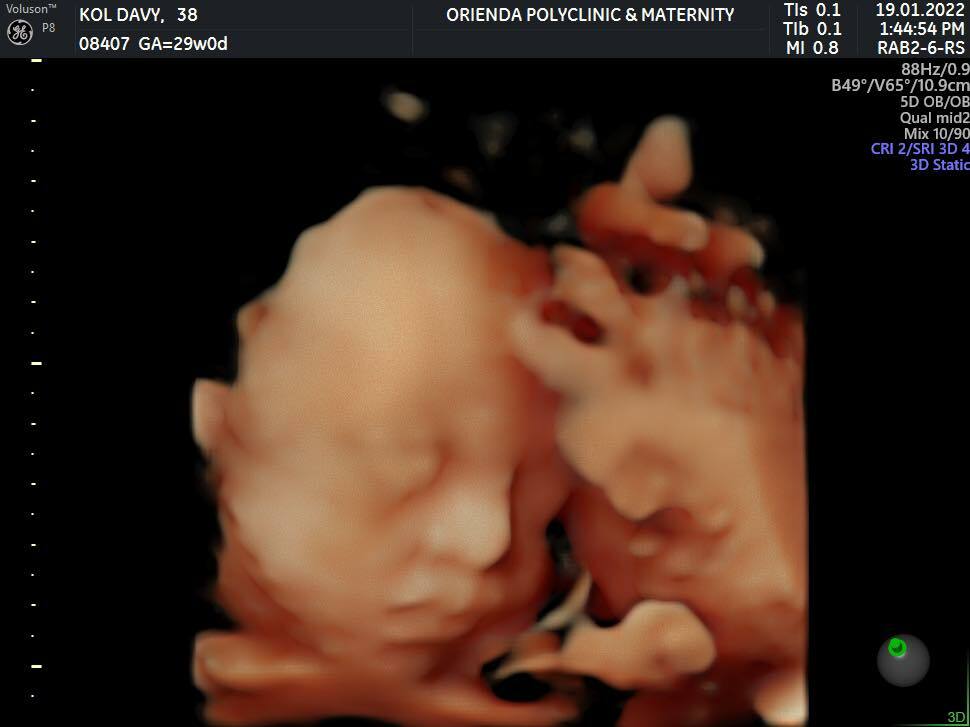

បន្ទាប់ពីមានការថ្លោះធ្លោយចំពោះកូនក្នុងផ្ទៃម្តងរួចមក ប្តីប្រពន្ធអ្នកសិល្បៈ លោក សុខ រក្សា និងអ្នកនាង កុល ដាវី មិនបណ្តោយឱ្យមានការថ្លោះធ្លោយម្តងទៀតចំពោះការមានផ្ទៃពោះជាលើកទី២នោះទេ បន្ទាប់ពីអ្នកទាំងពីរទទួលបានកាដូដ៏មានតម្លៃបំផុតក្នុងជីវិតជាលើកទី២ ដែលពេលនេះអនាគតអ្នកម្តាយ កុល ដាវី​ កំពុងតែពពោះជិតគ្រប់ខែ។ ពេលនេះ កូនក្នុងផ្ទៃរបស់អ្នកម៉ាក់ កុល ដាវី គឺជាកូនស្រី មានអាយុចូល៨ខែហើយ និងគ្រប់ខែនៅដើមខែមេសា ខាងមុខនេះហើយ។

អ្នកម៉ាក់ កុល ដាវី ត្រូវកេមើលឃើញថា កាន់តែស្រស់ស្អាតខ្លាំងឡើង ស្របពេលដែលកូនក្នុងផ្ទៃរបស់នាងមានអាយុកាន់តែចាស់ខែ ជាពិសេសនាងកាន់តែទទួលបានការថ្នាក់ថ្មម និងមើលថែរក្សាពីស្វាមីនាង គឺតារាចម្រៀង សុខ រក្សា ខ្លាំងឡើ់ងជារៀងរាល់ថ្ងៃ។ ជាក់ស្តែង តាមអ្វីដែលគេបានឃើញតាមបណ្តាញសង្គមហ្វេសប៊ុក នៅពេលដែលទៅទិញអីវ៉ាន់ និងទំនិញសម្រាប់កូនក្នុងផ្ទៃ សូម្បីតែកាបូបក៏ស្វាមីរូបនេះមិនឱ្យភរិយាកាន់ដែរ តែលោកជាអ្នកកាន់ជំនួស និងដើរតាមពីក្រោយ ដើម្បីមើលថែនាងយ៉ាងខ្ជាប់ខ្ជួន រហូតធ្វើឱ្យមហាជនអ្នកគាំទ្រ ពោលឡើងថា អ្នកនាង កុល ដាវី ពិតជាមានសំណាងខ្លាំងណាស់ដែលស្វាមីតាមមើលថែដិតដល់បែបនេះ។